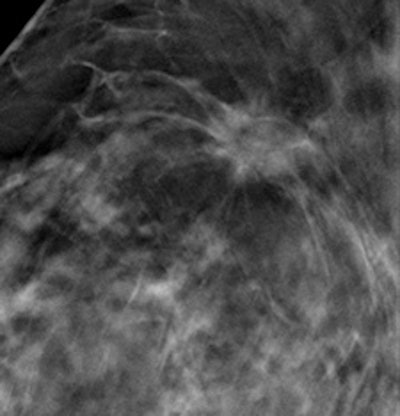

Example of improved screening with 3D imaging with tomosynthesis -- a cancer stellate opacity with distortion with tomosynthesis (right) and with standard mammography (left)."We found that tomosynthesis as a triage in recalled cases reduced [recall rates] and did not cause any false-negative recommendations," the researchers concluded.